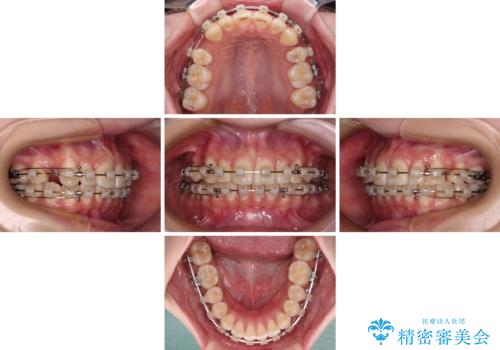

- クリアブラケット

- 2年2ヶ月

- 10-30回

- 口を閉じたときに唇の間から飛び出してくる前歯を気にして来院された患者様です。

骨格的に上顎骨が前方位にあるため、左右の第一小臼歯を抜歯し、ワイヤー装置にて咬み合わせを整えていくこととしました。